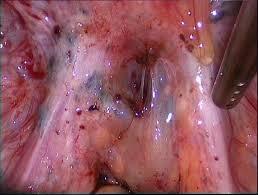

После того, как мы сделали анестезию, мы по необходимости производим разрез и отслаиваем слизистую оболочку с надкостницей от кости (слизисто-надкостничный лоскут) и бормашиной с водяным охлаждением выпиливаем костную стенку. Почему по необходимости? Потому что эти этапы зависят от степени прорезанности и расположения зуба. Чем более прорезан зуб, тем меньше разрез и меньше убираем кости. Иногда обходимся одним разрезом, иногда даже разрез не приходится делать, а просто распиливаем зуб. Короче, смотрим по ситуации.

По необходимости распиливаем сам зуб. Опять по необходимости? Конечно! Ведь надо смотреть по ситуации и соблюдать баланс между травматичностью и скоростью проведения операции. Если зуб лежит только под слизистой, корни сросшиеся и его можно достать элеватором, то не надо лишний раз его пилить. Достали, зашили и отпустили домой. Если же у нас зуб лежит криво и достать него просто так не получается, то тогда уже пилим либо зуб, либо подпиливаем кость.

После того как все удалили, мы чистим лунку от опилок и осколков, убираем оболочку фолликула, если он имел место быть, моем антисептиком. Обязательно пальцем щупаем на предмет острых краев лунки, чтобы потом они не прорезались. Если торчат, то убираем.

После обработки лунки мы кладем в неё либо гемостатическую губку, либо тромбоцитарную массу.

Если мы резали и откидывали слизисто-надкостничный лоскут, то кладем его обратно, и фиксируем швами. После швов обязательно контролируем остановилась ли кровь. Поэтому если врач сказал, что шов последний, не надо резко вскакивать и убегать.